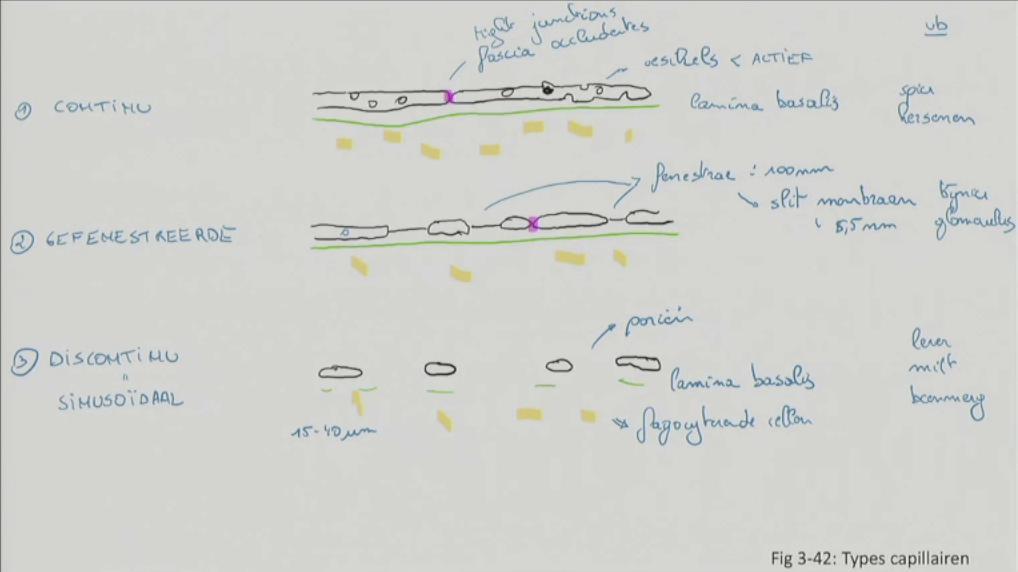

Fig 3.42: Types capillairen

A continu

grondsubstantie (geel) lamina basalis (groen, continu) endotheel vesikels fascia occludentis =? tight junctions (paars) voorbeelden: spieren, hersenen

B gefenestreerd

grondsubstantie (geel) lamina basalis (groen, continu) endotheel tight junctions (paars) -

fenestrae (100 nm)

voorbeelden: glomerulus in nier, bijnier

C discontinu = sinuoidaal

-

grotere diameter (15-40 um)

grondsubstantie (geel) lamina basalis (groen, onderbroken) endotheel porien fagocyterende cellen voorbeelden: lever, milt, beenmerg

|

welk soort capillair?